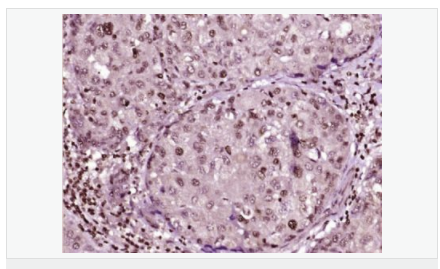

產品應用ELISA=1:5000-10000 IHC-P=1:100-500 IHC-F=1:100-500 Flow-Cyt=1μg/Test ICC=1:100 IF=1:100-500 (石蠟切片需做抗原修復)

image.png